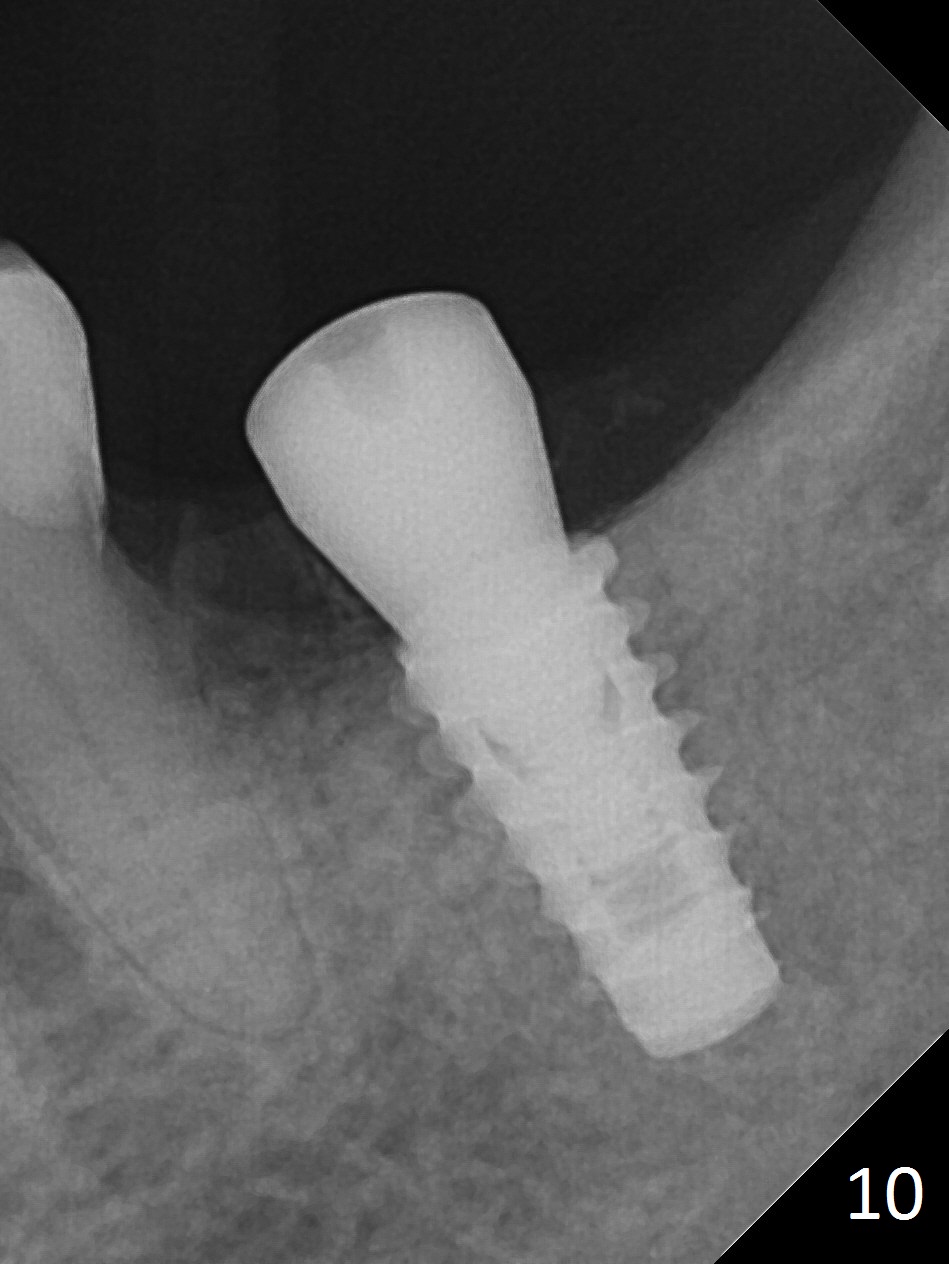

There is no apparent bone loss 4 months postop (Fig.10). There is chewing pain in spite of occlusal adjustment 7 months post cementation (Fig.11-13: increased radiolucency around the implant). The crown/abutment is removed and a healing abutment is placed (6x3 mm); the implant is stable. The patient return for re-evaluation in 3 months (15 months postop); radiolucency appears to reduce (Fig.14). But there is pain when the healing abutment is being removed. After local anesthesia, the implant is removed with a wrench. Following debridement of the osteototomy (intact, although tender), a 5x10 mm dummy implant with SLA surface is placed (Fig.15). After 5.5 mm tap, a 5.5x8.5 mm implant is placed with >50 Ncm (Fig.16). A 6.8x5 mm healing abutment is placed, followed by periodontal dressing. Re-analysis of preop CBCT shows that the bone density at the site is low: 70 units average. Progressive loading is necessary for this case 4-6 months postop. The soft and hard tissues around the implant seem to heal 4 months postop (Fig.17).